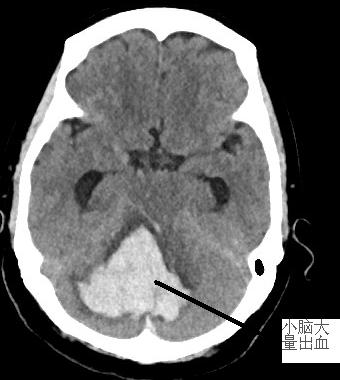

患者徐阿婆,71歲,3月13日約11時(shí)被發(fā)現(xiàn)躺于田野中,呼之不應(yīng)。家屬趕緊將其送至我院急診科。通過腦部CT掃描出小腦大量出血,出血量約30ml,小腦半球、小腦蚓、腦干(生命中樞)受壓,環(huán)池變窄,且患者處于昏迷狀態(tài),雙側(cè)瞳孔對(duì)光反射遲鈍,情況危急。為搶救生命,需要進(jìn)行開顱手術(shù)治療。我院神經(jīng)外科醫(yī)生謝志芳告知家屬病情后,家屬考慮到徐阿婆年紀(jì)較大、經(jīng)濟(jì)狀況不佳等情況,對(duì)是否進(jìn)行手術(shù)猶豫不決。

我院神經(jīng)外科在做好積極術(shù)前準(zhǔn)備的同時(shí),聯(lián)系福醫(yī)大附二院神經(jīng)外科當(dāng)值專家。專家到位后立即將患者送入手術(shù)室。術(shù)中見小腦膨脹明顯,壓力高,予充分清除血腫后,腦組織壓力減低,腦血管搏動(dòng)有力。術(shù)后,患者生命征平穩(wěn)。

左圖為術(shù)前顱內(nèi)血腫,右圖為術(shù)后原血腫位置。

復(fù)查CT后,徐阿婆小腦內(nèi)血腫基本清除,壓力下降。后續(xù)在我院神經(jīng)外科與福醫(yī)大附二院神經(jīng)外科專家聯(lián)合治療下,病情好轉(zhuǎn),4月12日痊愈出院。